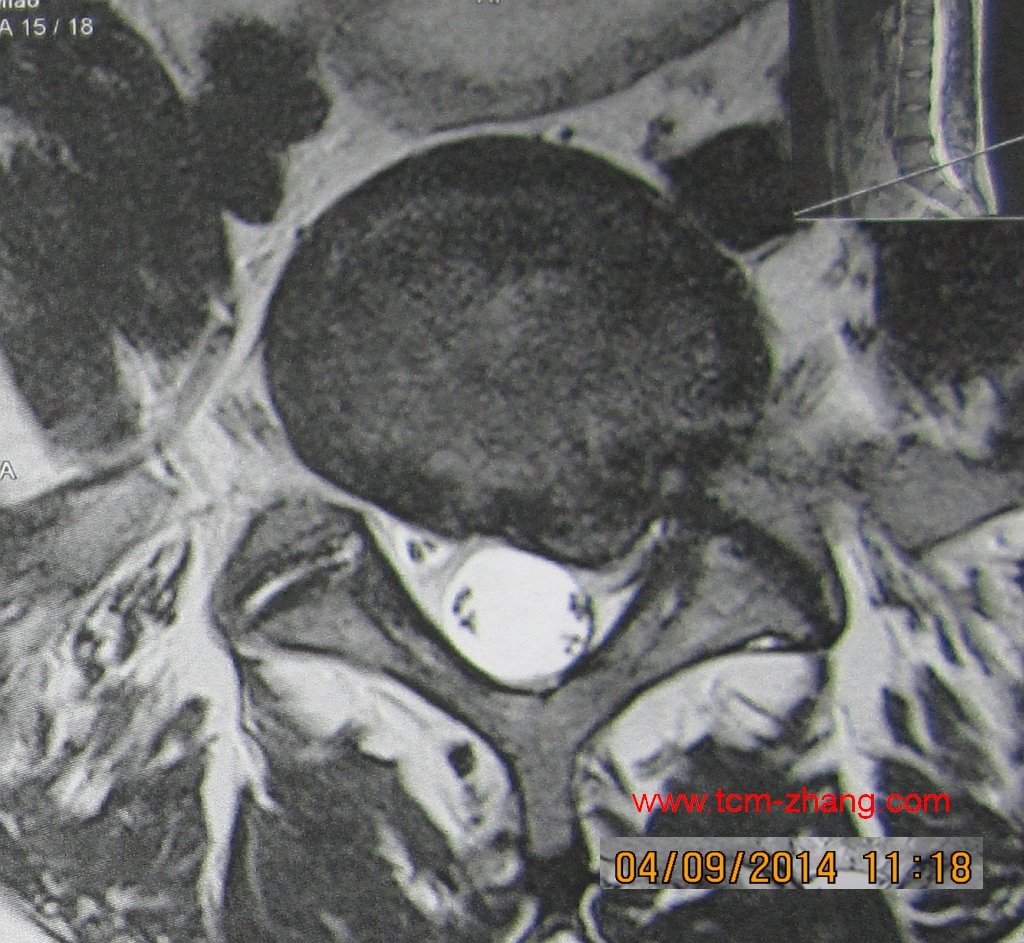

- Herr Li schreibt (26.10.2014):

L4/5 Prolaps eindeutige Wurzelkompression, nach 4. Behandlungen schmerzfrei!